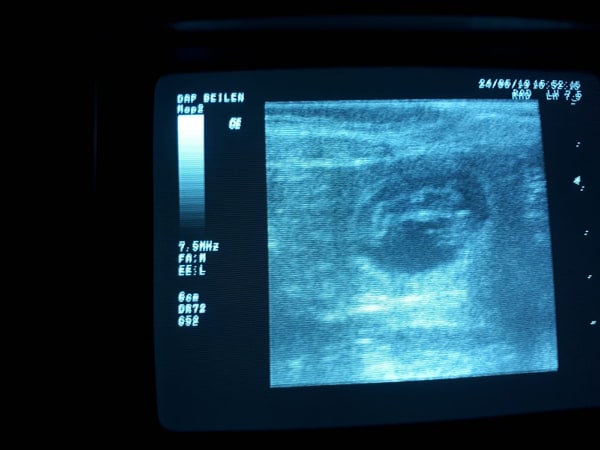

Dracht Vier weken na de date van Guus en Luna een echoLuna is drachtig. In de laatste week voor de bevalling zien we op een röntgenfoto dat Luna maar 1 pup draagt Dit delen: Delen op X (Opent in een nieuw venster) X Share op Facebook (Opent in een nieuw venster) Facebook Vind-ik-leuk Aan het laden...